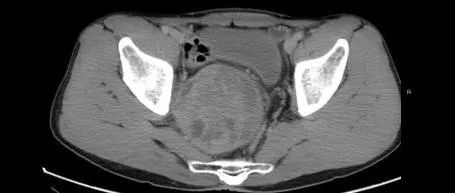

男性,肛门周围坠胀8天,请诊断!

医学影像  yxyx-app  医学影像APP,打造伴随医生快速成长的影像学习社区。与影像园(Xctmr.com)一起提供最全面的影像案例库、基础(解剖、病理、影像诊断)知识、影像技术及考题等,为医生提供最佳的医学影像参考。【所属科室】普外科【基本资料】患者,男,49岁【主诉】肛门周围坠胀8天【现病史】患者8天前自觉肛门周围坠胀,伴大便较前明显变细,色黄,当地医院提示盆腔包块,6天前自觉坠胀加重。直肠指捡:肛门右侧触及一质软包块。...

医学影像APP 2021-12-17